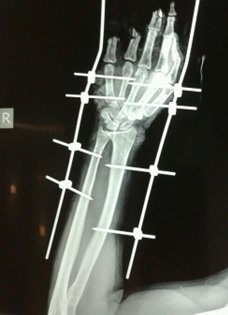

Partial Hand Amputation

Hand Fracture Fixation